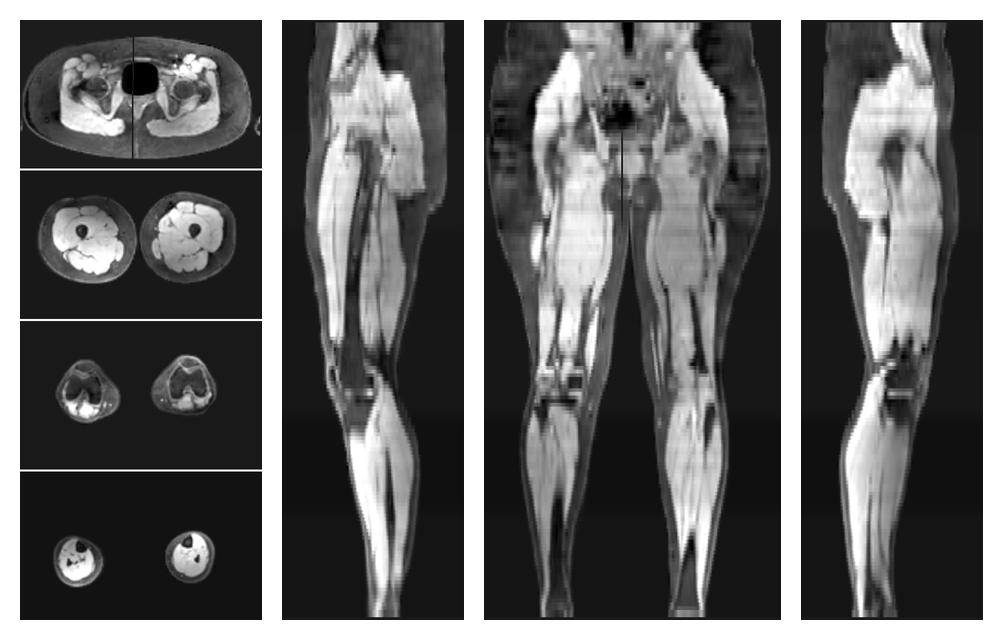

• Water only signal

The water part of the acquired multi-echo spin echo data.